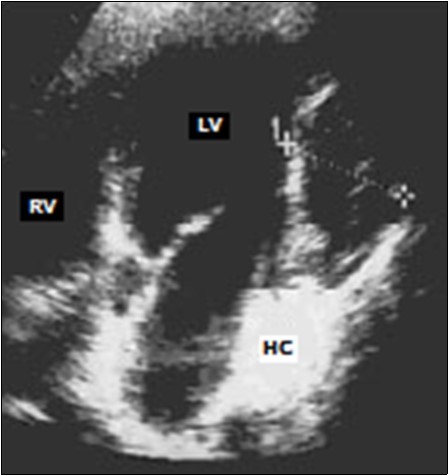

Transthoracic echocardiography showed an intra-myocardial mass localized in the infero-posterior wall of the left ventricular. This mass was well-defined, oval-shaped, echogenic, heterogeneous, measuring 37 × 62mm long axes, and largely calcified (Figure 2).

Figure 2.Trans-thoracic echocardiography: echogenic, heterogeneous mass of the infero-posterior wall of the left ventricle (LV: left ventricle, RV: right ventricle, HC: hydatid cyst).